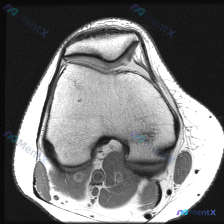

看到这个病例,临床关注点是「膝关节软骨异常」,只拿到了这一张膝关节MRI T1加权轴位图像,整理一下分析思路给大家参考。 一、病例基本影像信息 这是一张股骨远端层面的轴位T1加权图像,先整理一下能看到的信息: 1. 骨结构:股骨内侧髁、外侧髁轮廓清晰,皮质骨连续低信号,骨髓腔内中等信号符合正常表现,...